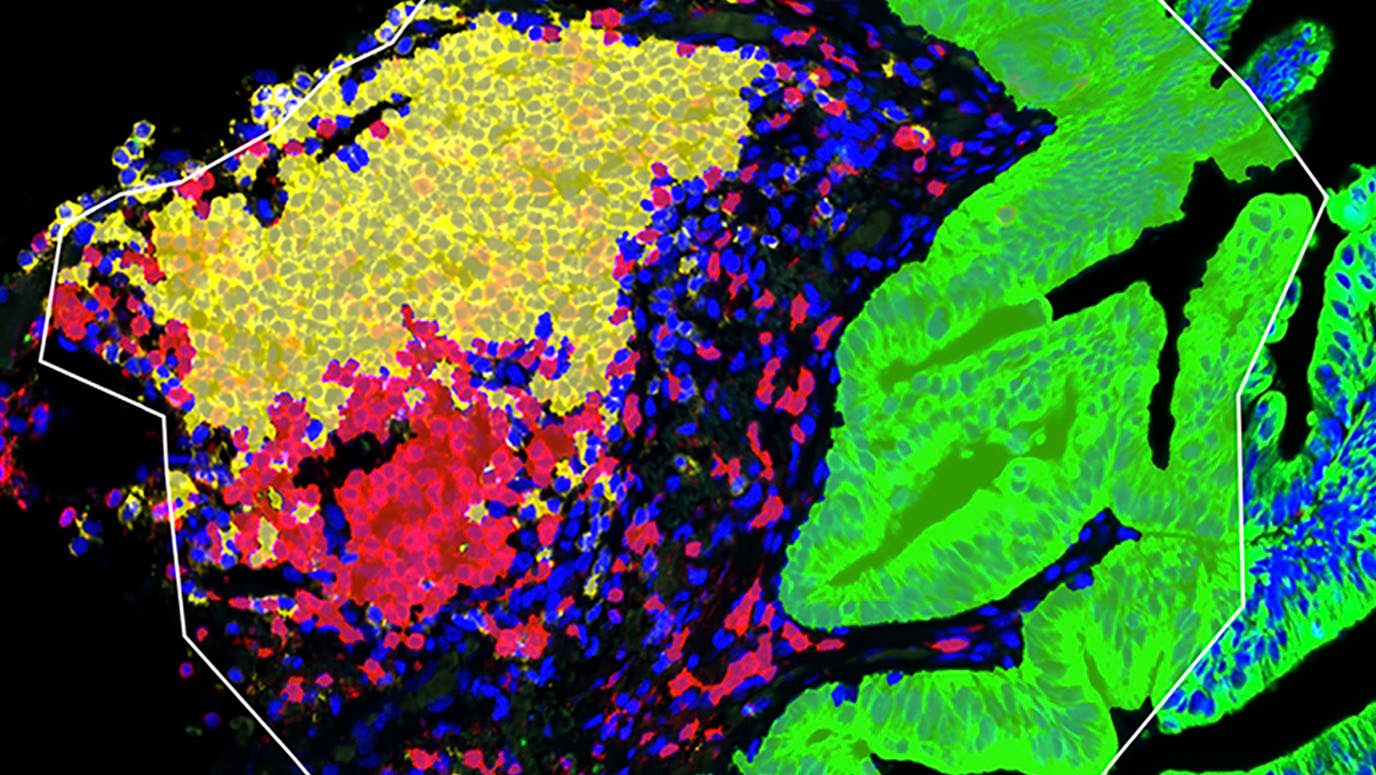

Tumor-infiltrating B cells and plasma cells influence early-stage lung cancer biology, immunotherapy responses

Through extensive single-cell analysis, researchers at The University of Texas MD Anderson Cancer Center have created a spatial map of tumor-infiltrating...